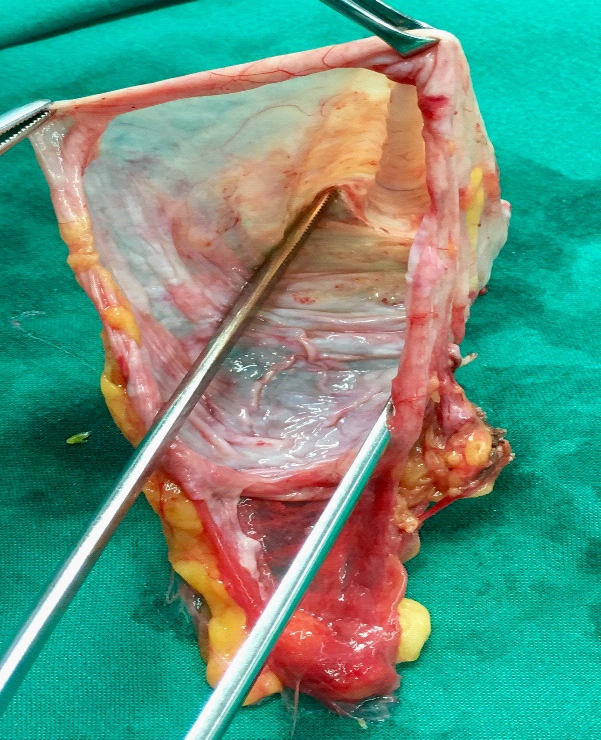

Multidisciplinary team (MDT) meeting recommended to attempt laparoscopic approach; since investigations revealed no biologic or radiologic potentially malignant features. Patient was consented for laparoscopic cholecystectomy and resection of the cystic mass with the possibility of conversion to laparotomy. She was placed in the reverse Trendelenburg with right up tilt position and the procedure was performed using three trocars only (two 5 mm and one 10 mm ports). Initial exploration revealed a large bulge within the mesentery of the right colon (Figure 2). Liver and peritoneal surfaces were examined and noted no abnormality. Adequate exposure was attained using Cattel maneuver (medial visceral rotation of right-sided organs). The uterus and both ovaries looked normal, no attachment with the cyst was identified. Gallbladder was retracted upward and the large cystic lesion was entirely visualized. It appeared to be an oval, thin walled and transparent. It had a regular border with smooth glistening surface containing about 500 ml of serous material. Cyst was easily separable from the adjacent organs. It was totally dissected from the inferior border of the liver and right kidney down to the right iliac fossa. Complete excision of the cyst was done followed by cholecystectomy. The cyst wall components and gallbladder were retrieved through the umbilicus (Figure 3). All her symptoms were disappeared after surgery.

Figure 3:Gross Appearance of the cyst.